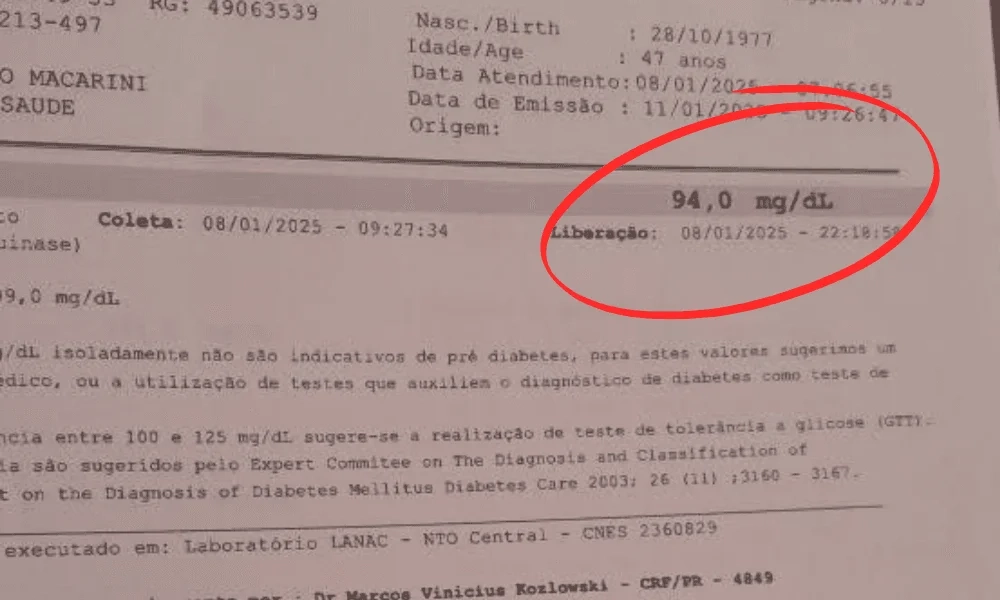

Endocrinologista revela a verdade sobre medicamentos convencionais e mostra como manter a glicemia abaixo de 100 mg/dL – de forma natural e segura

“Eu sou a Luzinete Lima e passei 15 anos lutando com minha glicemia, que sempre estava acima de 400 mg/dl. A preocupação com minha saúde era constante e eu vivia com medo do futuro.

Mas, três meses depois de começar a usar o BIOGOTA, minha realidade começou a mudar drasticamente. Consegui estabilizar minha glicemia para 94 mg/dL além de perder 8 kg de gordura localizada.

E após 6 meses de uso eu percebi que os sintomas haviam sumido de vez, a glicose estabilizou, as dores no corpo sumiram e finalmente fiquei curada. O BIOGOTA não só controlou minha diabetes, mas recuperou minha saúde e qualidade de vida. Super recomendo!!”